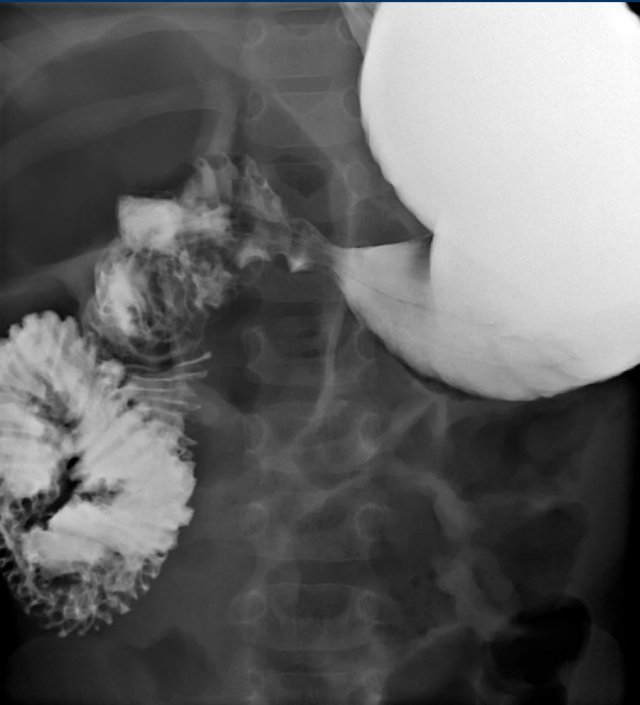

The upper GI-study shows a malrotation complicated by a volvulus.

This results in the typical corkscrew or reversed 3 sign.

An overfilled stomach could hide the corkscrew on the AP projection so the stomach should first be aspirated by use of a nasogastric tube and the volume of injected contrast should be small.